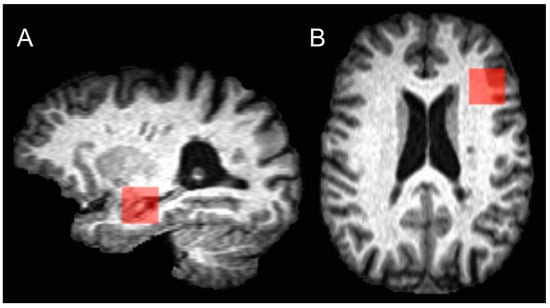

2.3. MRI Acquisition and Analysis